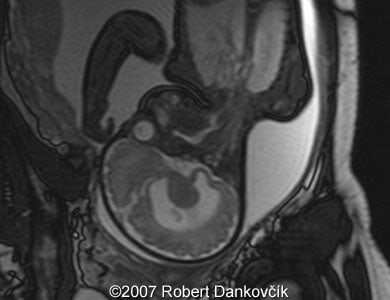

Images 8, 9: MRI; 32 week of pregnancy; transverse sections through the fetal skull showing dilated lateral ventricles and dominant interhemispheric cyst extending to the right.

9

10

Images 10, 11: MRI; 32 week of pregnancy; transverse (image 11, left) and parasagittal (image 12, right) sections through the fetal skull showing dilated lateral ventricles and interhemispheric cyst.

11

12